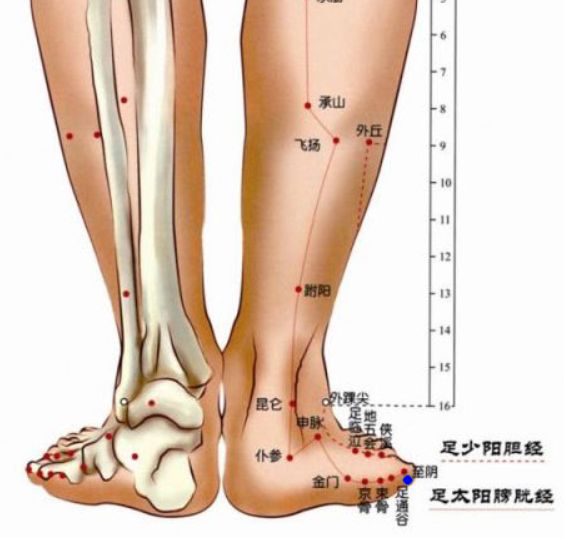

穴位图:

至阴

归经:

足太阳膀胱经

定位:

在足小趾末节外侧,距趾甲角0.1寸。